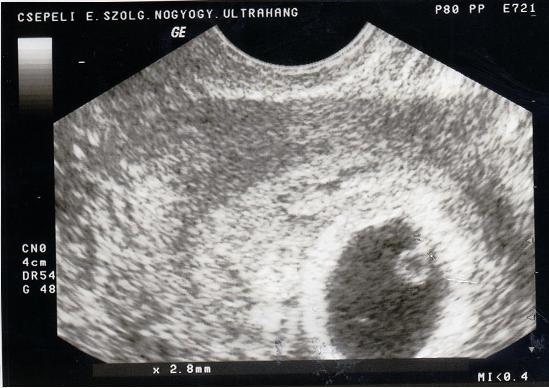

Kéthetente uh: én is úgy tudom, hogy tudományosan nem bizonyították a magzatra gyakorolt káros hatását, de nem lehet véletlen, hogy a várandósság alatt is 4-5 alkalomnál, problémásabb esetekben 8-10 alkalomnál nem nézik többször a babát a géppel. Persze egy fizetős uh-os orvos biztosan meg fogja csinálni...

UH: Én sem láttam még a babát, csak a hét végén győződhetek meg róla, hogy jó helyen van-e. Várom is meg nem is. Nem szeretnék csalódni. Hülyeség nem?

Ha vmi nem stimmel, inkább most derüljön ki, mint később.